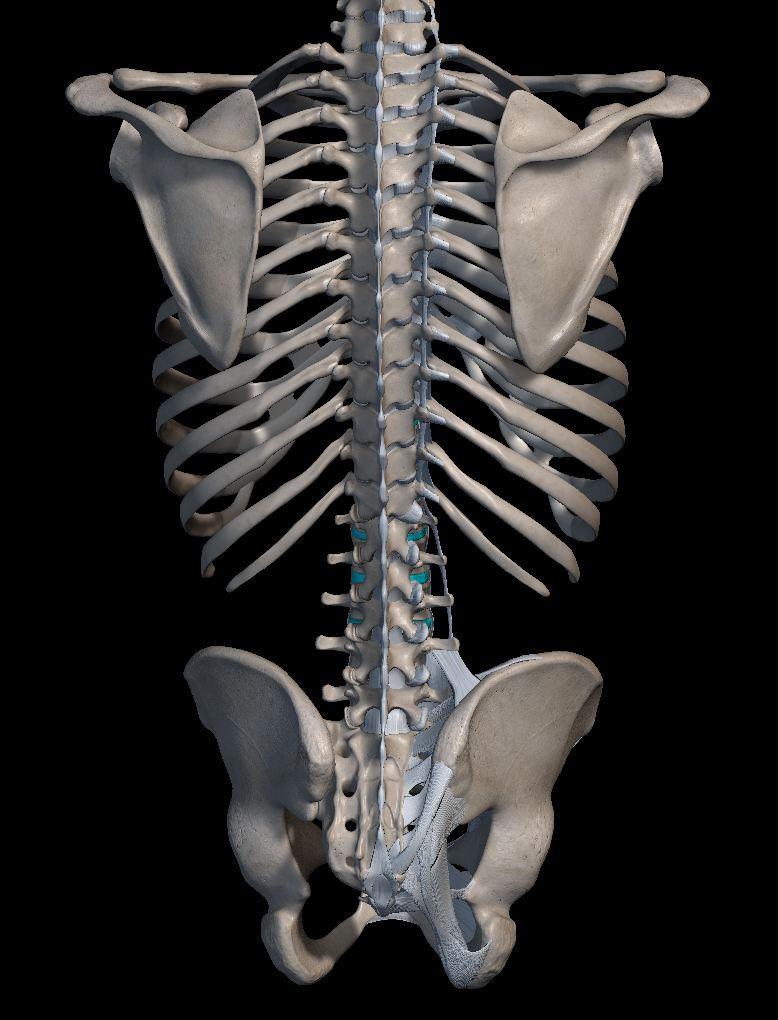

강직성 척추염은 주로 척추, 특히 꼬리뼈 부위의 천장 관절 쪽에 영향을 미치는 만성 관절염의 일종이지만 경우에 따라 다른 관절에도 영향을 미치곤 합니다.

'강직성 척추염'은 명칭 그대로 허리 부위에 염증이 생겨 움직임이 둔해지는 병이라고 생각하시면 됩니다. 하지만 척추의 유연성과 가동 범위에 제한이 걸리면서 어깨, 무릎, 발목 등의 다른 관절에도 통증을 일으키곤 하지요.